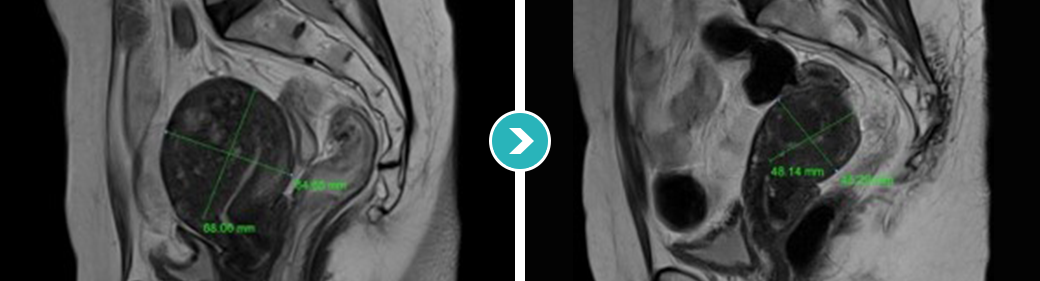

3STEP HIFU PROGRAM 2010년 부터 오직 자궁근종과 자궁선근증의 안전한 치료를 위해 전 과정MRI통합 하이푸 치료 프로그램 운영

시술 전 악성화 병변으로의 변화의 가능성 확인 및 숨어있는

악성 병변을 분석하는 MRI 촬영

시술과정 초음파영상과 MRI영상 콜라보 모니터링

시술 후 하이푸 치료 브리핑 및 객관적 평가

MRI촬영으로 자궁근종의 상태(위치, 개수, 크기, 모양 등), 자궁근종의 혈액공급 및 혈류,

자궁근종과 인접한 주요장기 및 구조, 초음파 발사경로의 확보 등을 분석함. 또한, 정밀초음파는 제거할 자궁근종의 개수, 자궁근종의 치료 슬라이스 수와

각 슬라이스의 체적, 근종제거마진, 근종과 인접한 장기와의 상관관계 등을 분석합니다.

전사적으로 시행함으로써 하이푸 시술의 안전도와 치료효과를 높이는 통합 MRI하이푸 프로그램입니다.

시술 전 MRI검사 결과를 바탕으로 자궁근종이나

자궁선근증 등 종양의 위치, 크기, 모양 등 정확하게 파악